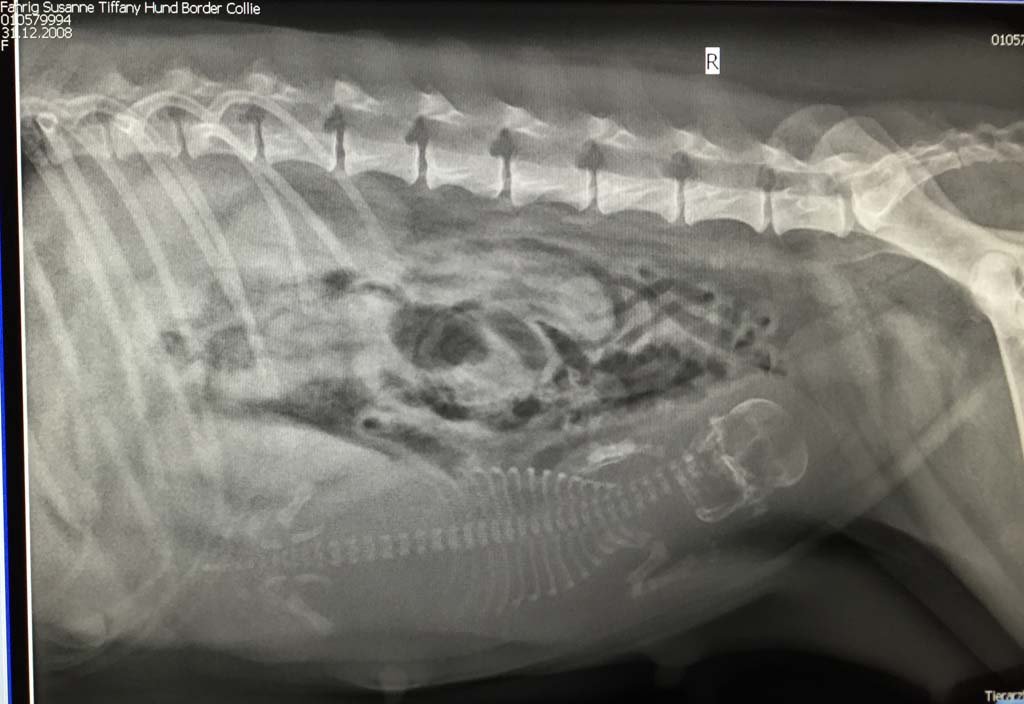

Diese Aufnahme entstand am Tag 58 der Trächtigkeit.